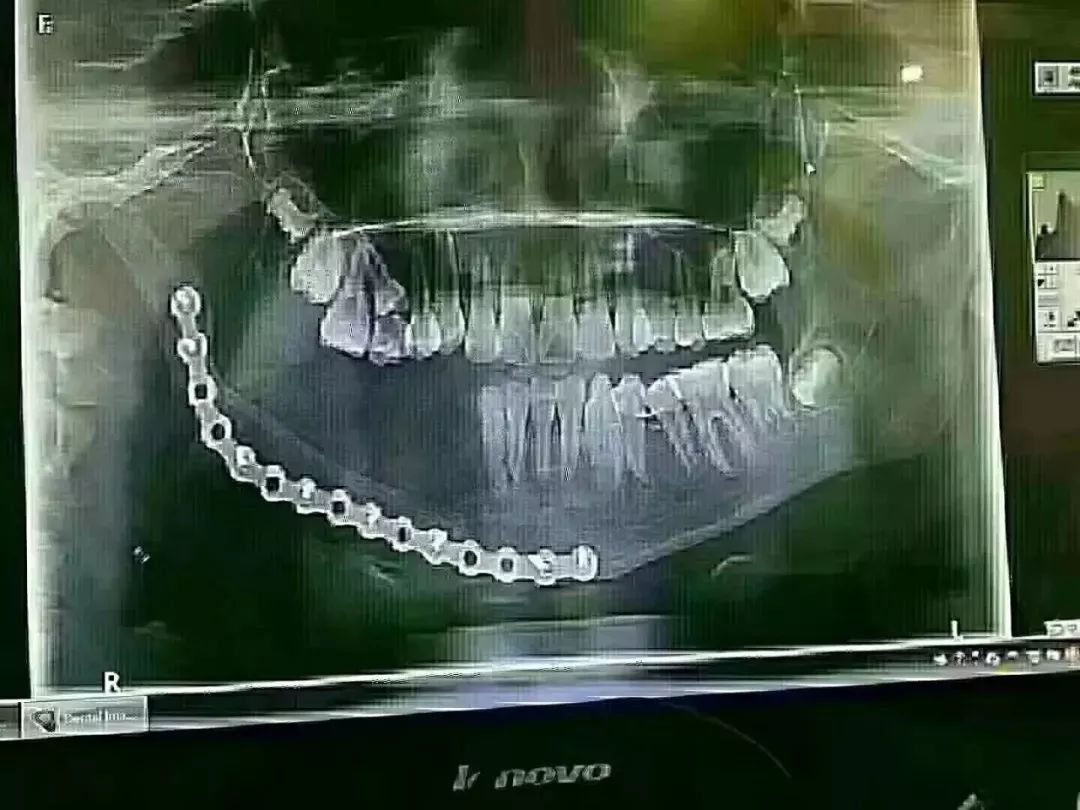

小姑娘年仅12岁,因乳牙龋坏太严重,引起下颌大面积囊肿,没办法只得做了下颌骨切除手术,手术费用花了16万元,不过现在都恢复的挺好的,只是右边下边没牙了。